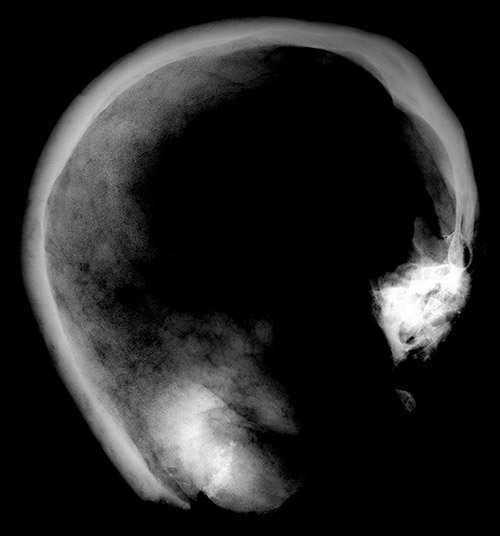

Figure 2

Skull with intensely calcified bone proliferation at the right side of the os frontalis.

The remains are well preserved. Morphological examination of skull and pelvis clearly classify the individual as female. The age at death was between 30 and 50 years. There is an intensely calcified bone proliferation at the right side of the os frontalis (fig. 2). Plain X-ray and CT imaging show a large (5.3 x 3 x 8.7 cm) sclerotic lesion in the area of the right temple with a partly bulging appearance (fig. 4). Figure 5 shows representative slices of the admission CT. A differentiation between tabula interna, diploë and tabula externa is not possible in major parts of the lesion. The inner boundary of the lesion shows multiple smooth-edged irregularities. There is a diffuse thickening of the right skull vault (right 7 mm, left 4 mm). The left skull vault presents a mix of sclerotic areas and areas with normal appearance with a clear differentiation between tabula interna, diploë and tabula externa. CT imaging and plain X-ray show a wedge-shaped area in the centre of the lesion that is filled with material of lower X-ray density than the adjacent bone (figs 5 and 6). Histology shows mature organised lamellar bone tissue with ordered formation of trabeculae (figs 7–9). No pathological alterations were found in the postcranial bones.